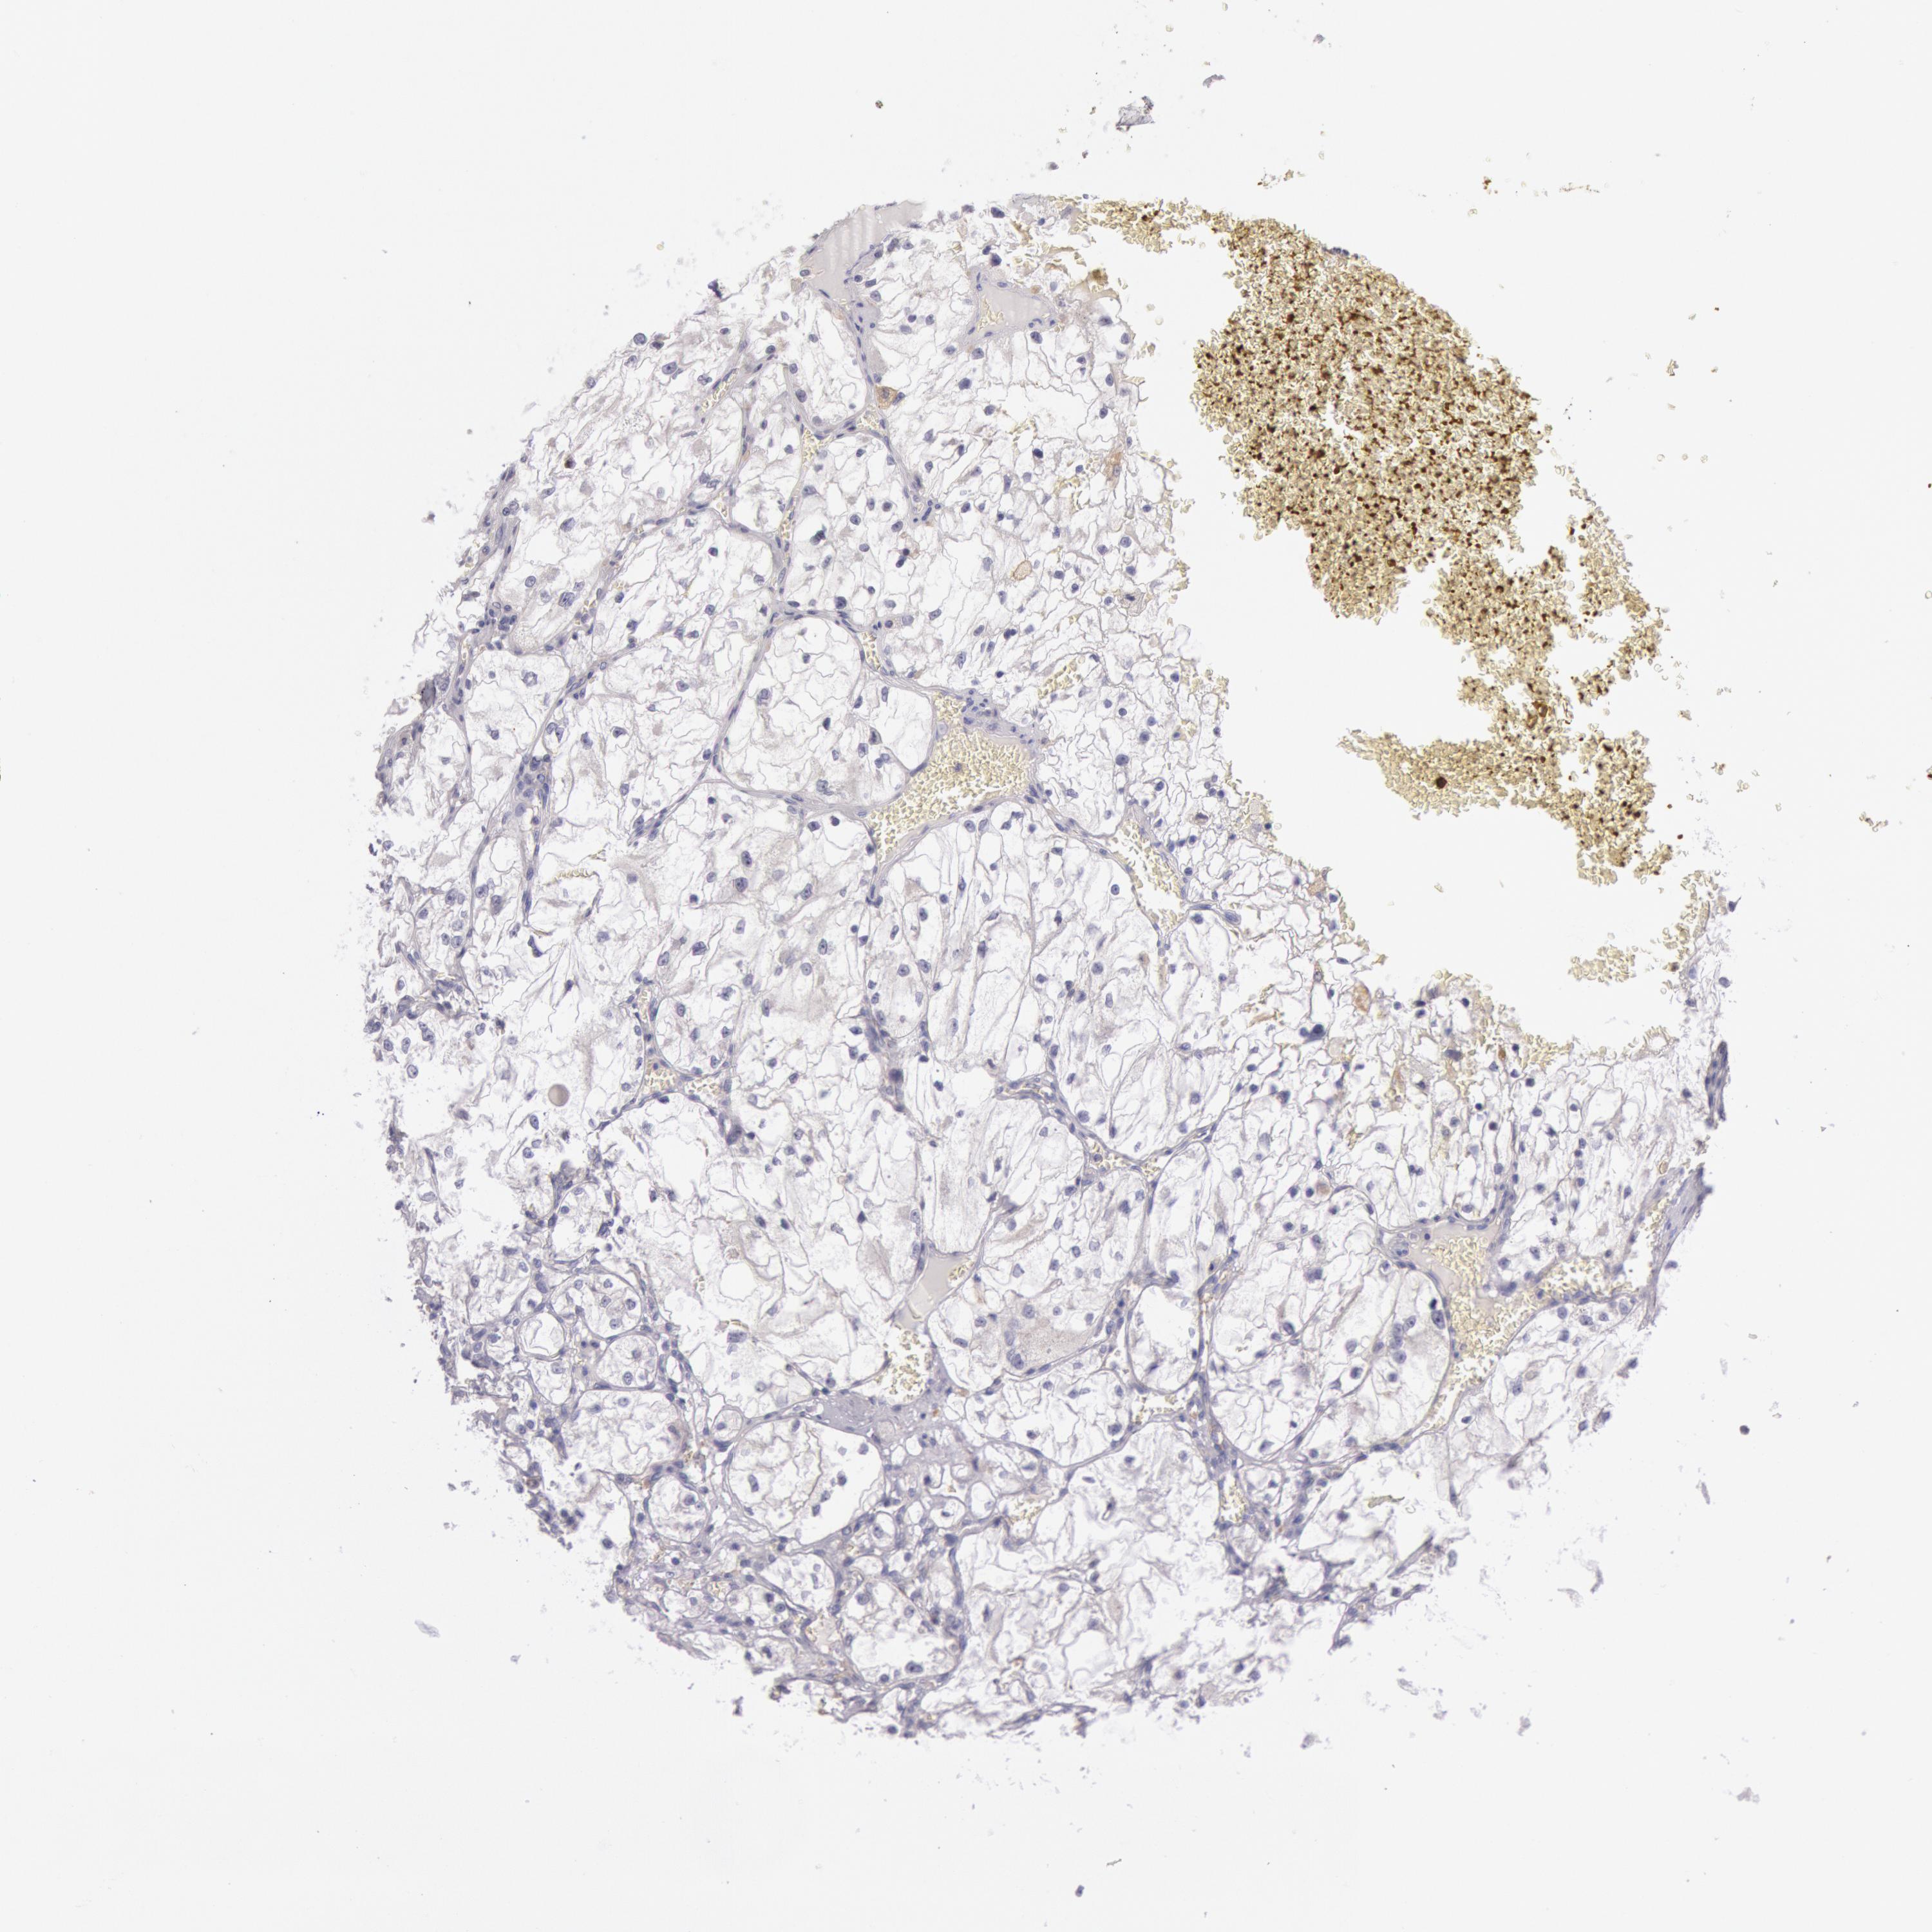

KIDNEY RENAL PAPILLARY CELL CARCINOMA (TCGA) - Interactive survival scatter ploti

The Survival Scatter plot shows the clinical status (i.e. dead or alive) for all individuals in the patient cohort, based on the same data that underlies the corresponding Kaplan-Meier plots. Patients that are alive at last time for follow-up are shown in blue and patients who have died during the study are shown in red.

The x-axis shows the expression levels (FPKM) of the investigated gene in the tumor tissue at the time of diagnosis. The y-axis shows the follow-up time after diagnosis (years). Both axes are complimented with kernel density curves demonstrating the data density over the axes. The top density plot shows the expression levels (FPKM) distribution among dead (red) and alive patients (blue). The right density plot shows the data density of the survived years of dead patients with high and low expression levels respectively, stratified using the cutoff indicated by the vertical dashed line through the Survival Scatter plot. This cutoff is automatically defined based on the FPKM cutoff that minimizes the p-score. The cutoff can be changed by dragging the vertical line or by entering a cutoff value in the square labeled "Current cut-off".

Under the Survival Scatter plot the p-score landscape (black curve; left axis) is shown together with dead median separation (red curve; right axis). Dead median separation is the difference in median mRNA expression between patients who have died with high and low expression, respectively. It is calculated as follows: median FPKM expression of dead patients with high expression - median FPKM expression of dead patients with low expression. This is intended to aid the user in visually exploring custom cutoffs and the associated p-scores and dead median separation.

Individual patient data is displayed and can be filtered by clicking on one or more of the category buttons on the top of the page. Categories describing expression level and patient information include: high, low, alive, dead, female, male and tumor stages. The scale of the x-axis can be toggled between linear and log-scale by clicking on the "x log" button. Mouse-over function shows TCGA ID, patient information and mRNA expression (FPKM) for each patient.

& Survival analysisi

Kaplan-Meier plots summarize results from analysis of correlation between mRNA expression level and patient survival. Patients were divided based on level of expression into one of the two groups "low" (under cut off) or "high" (over cut off). X-axis shows time for survival (years) and y-axis shows the probability of survival, where 1.0 corresponds to 100 percent.

MYO5A is not prognostic in Kidney Renal Papillary Cell Carcinoma (TCGA)